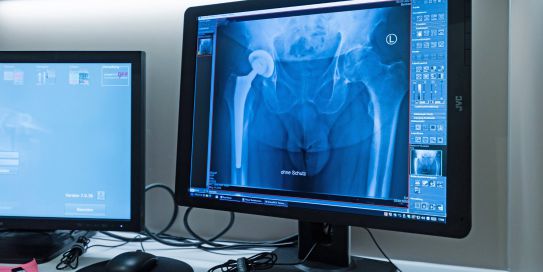

Die Röntgenuntersuchung ist nach wie vor das Standardverfahren zur Bildgebung in der Orthopädie und Unfallchirurgie. In der Praxis steht eine voll digitalisierte Röntgenanlage neuester Generation zur Verfügung. Damit kann die Strahlenbelastung bei den Aufnahmen auf ein Minimum reduziert werden. Darüber hinaus stehen die Bilder unmittelbar nach der Untersuchung zur Verfügung und können zur Optimierung der Bildqualität und damit für die Erkennung von Details am Computer entsprechend nachbearbeitet werden.